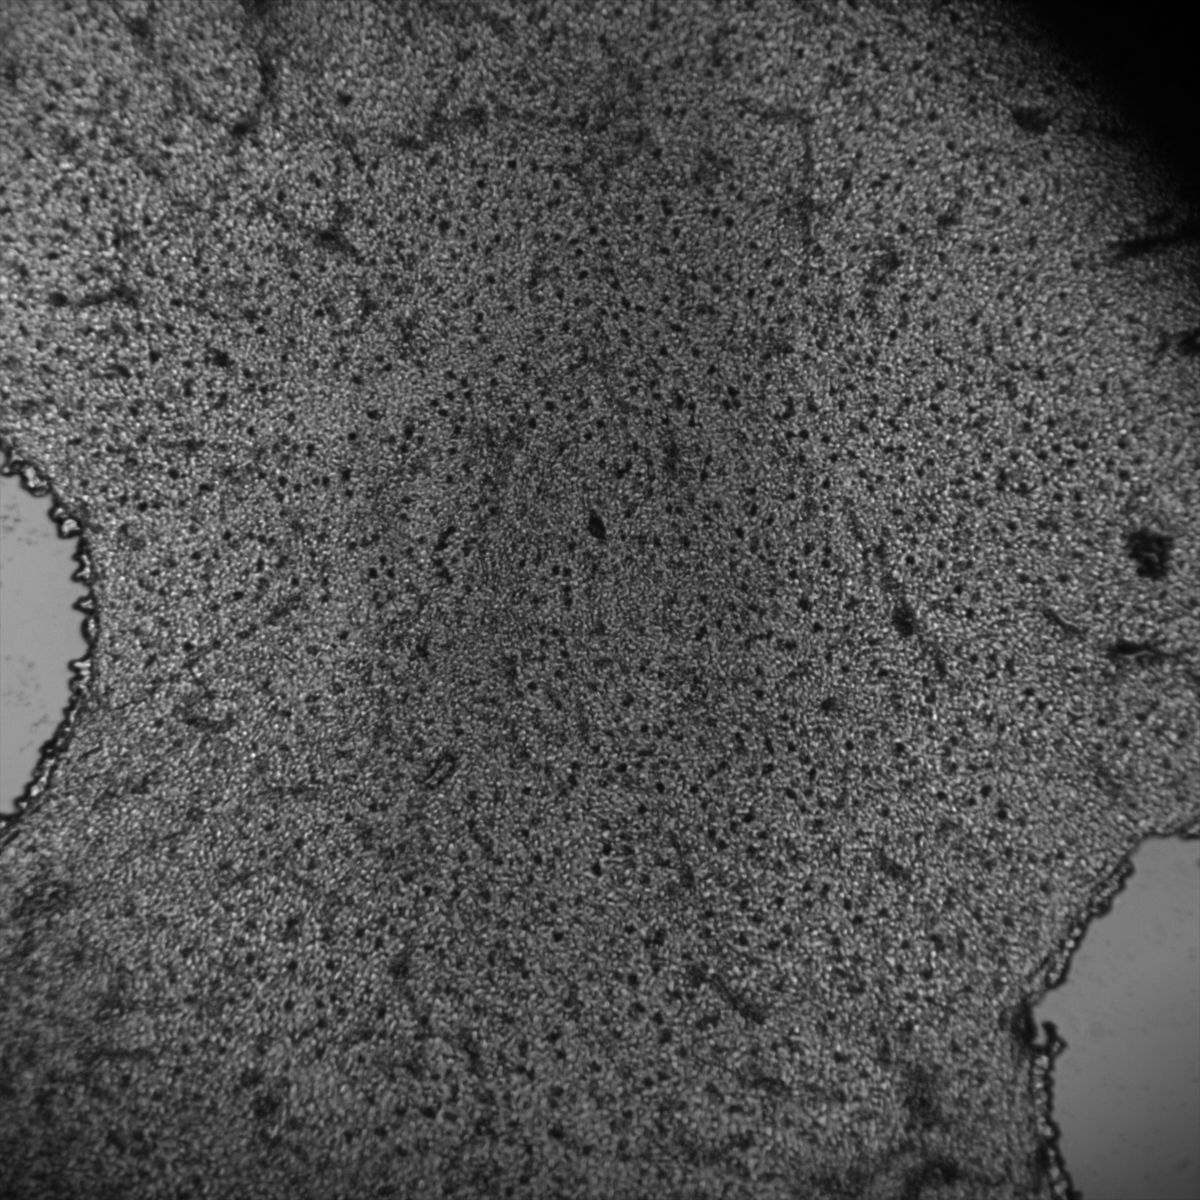

Muscle Cancer